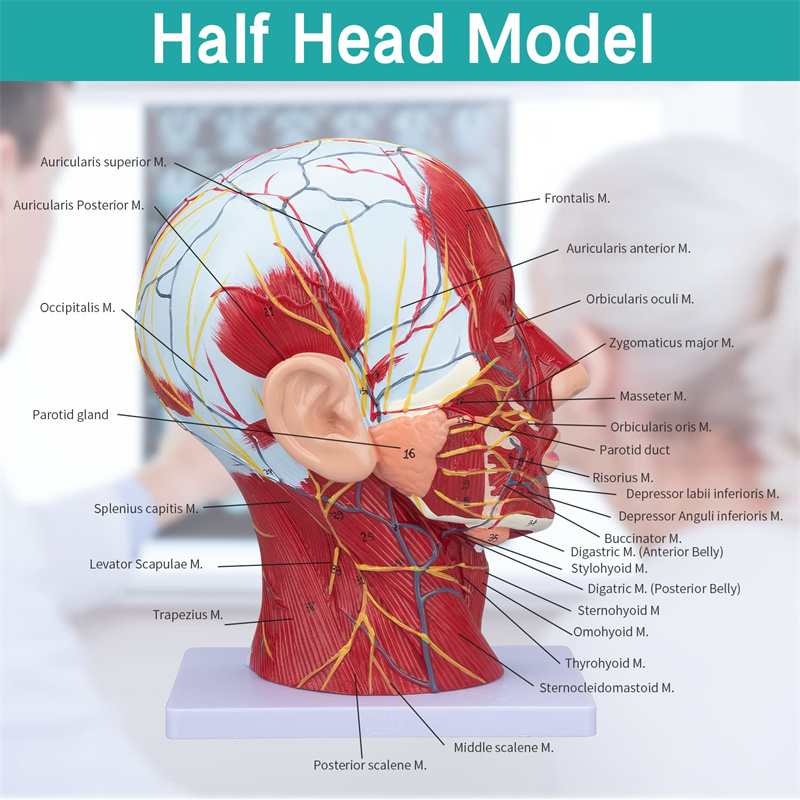

【Modelo superficial do músculo neurovascular】 Números altamente detalhados, marcados e destacáveis, aprofundar o entendimento dos músculos superficiais, vasos, nervos e as estruturas internas da cabeça e pescoço. Artéria vermelha, azul-veia, nervo amarelo.

【Apresenta】 mostra os músculos superficiais da face exposta; os vasos sanguíneos superficiais e os nervos do rosto e do couro cabeludo; as estruturas internas da glândula parótida e do trato respiratório superior; A estrutura de seção transversal sagital da coluna cervical.

Este modelo mostra detalhes do pescoço da cabeça direita e da seção sagital média do humano. incluindo o superficial

músculos da face exposta; os vasos sanguíneos superficiais e os nervos do rosto e do couro cabeludo; as estruturas internas

da glândula parótida e trato respiratório superior; A estrutura de seção transversal sagital da coluna cervical.

O modelo mostrou a morfologia local das seções sagitais mediais e laterais da cabeça e pescoço e suas estruturas vasculares e nervosas, com um total de 100 indicadores do local.

Este modelo é um modelo muscular neurovascular superficial grande e pescoço natural, um componente 1, mostrando os detalhes da cabeça e pescoço direito humano e seção sagital mediana, incluindo os músculos superficiais expostos da face, vasos superficiais do rosto e do couro cabeludo, nervos e a estrutura medial da glândula parótida e do trato respiratório superior, e a estrutura da seção sagital da coluna cervical